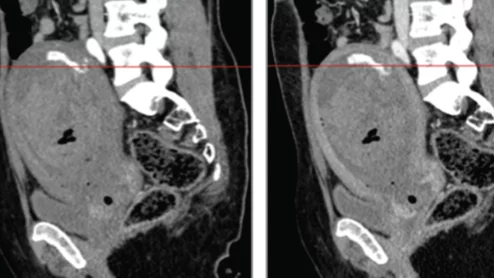

artificial intelligence in healthcare

artificial intelligence AI in healthcare